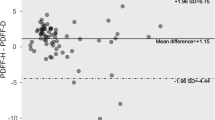

Correlation between SVS and each MRI-PDFF method showed overall good agreement (r = 0.909–0.977). The strongest correlation was found between SVS and VOI-PDFF (r = 0.977, p < 0.001) (Fig. 2). Free-drawn-PDFF-2 of the right lobe also showed good correlation (r = 0.970, p < 0.001). Free-drawn-PDFF-2 of the left lobe showed the worst relative correlation (r = 0.909). Figure 3 shows Bland–Altman plots between VOI-PDFF and segmental-PDFF, VOI-PDFF and free-drawn-PDFF, free-drawn-PDFF and segmental-PDFF, and free-drawn-PDFF and free-drawn-PDFF-2. Among them, the Bland–Altman plot comparing fat percentage with VOI-PDFF and segmental-PDFF showed the highest mean difference and widest 95 % limits of agreement (0.32 and −2.02, −2.65 %, respectively). The 95 % limits of agreement between the fat percentage of free-drawn-PDFF and free-drawn-PDFF-2 was the narrowest in this study (−0.82 to −1.39 %).

Bland–Altman plot representing the difference between VOI-PDFF, segmental-PDFF, free-drawn-PDFF, and free-drawn-PDFF-2. Among them, the plot between free-drawn-PDFF and free-drawn-PDFF-2 demonstrates the best agreement (mean difference, 0.29 %; 95 % Bland–Altman limits of agreement, −0.82 to 1.39 %)